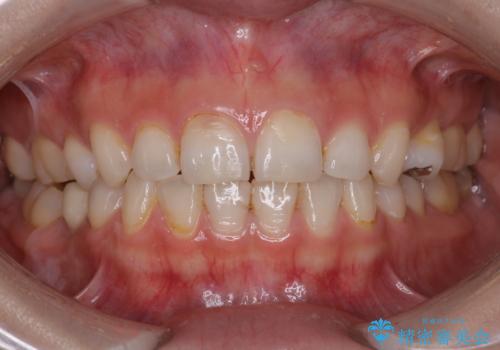

- 検査の結果、虫歯が見つかった患者様です。

適合の良いセラミックインレーで修復することで見た目の綺麗さを保ったまま治療することができます。